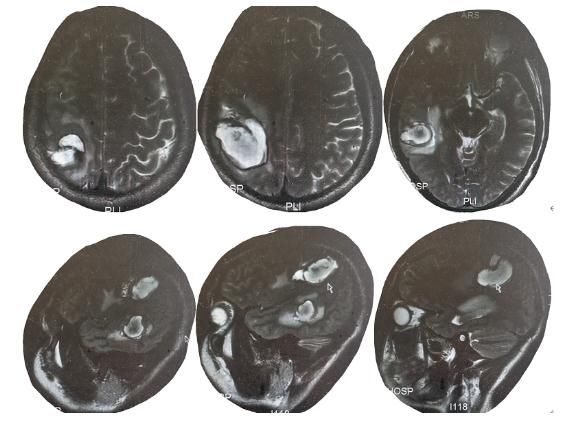

由于身体状态影响了工作,罗某只得到医院检查。原本以为只是感冒,医院的检查结果着实把他吓了一跳:头颅CT见左顶叶出血,凝血功能严重异常,嗜酸性粒细胞高达57.4%(正常值为0.5-5)。

4月22日,因病情严重,罗某被送往遵义医科大学附属医院。医院急诊科刘同英医生说,罗某颅脑CT右侧颞顶叶脑出血、右侧颞顶叶脑水肿,左侧肺少量液气胸、右侧肺有少量胸腔积液。此外,他的肝右叶也受到了损伤。结合检查结果,医生讨论后认为,罗某生活在寄生虫感染区,有疫水接触及生吃螃蟹的情况,考虑其感染了寄生虫。